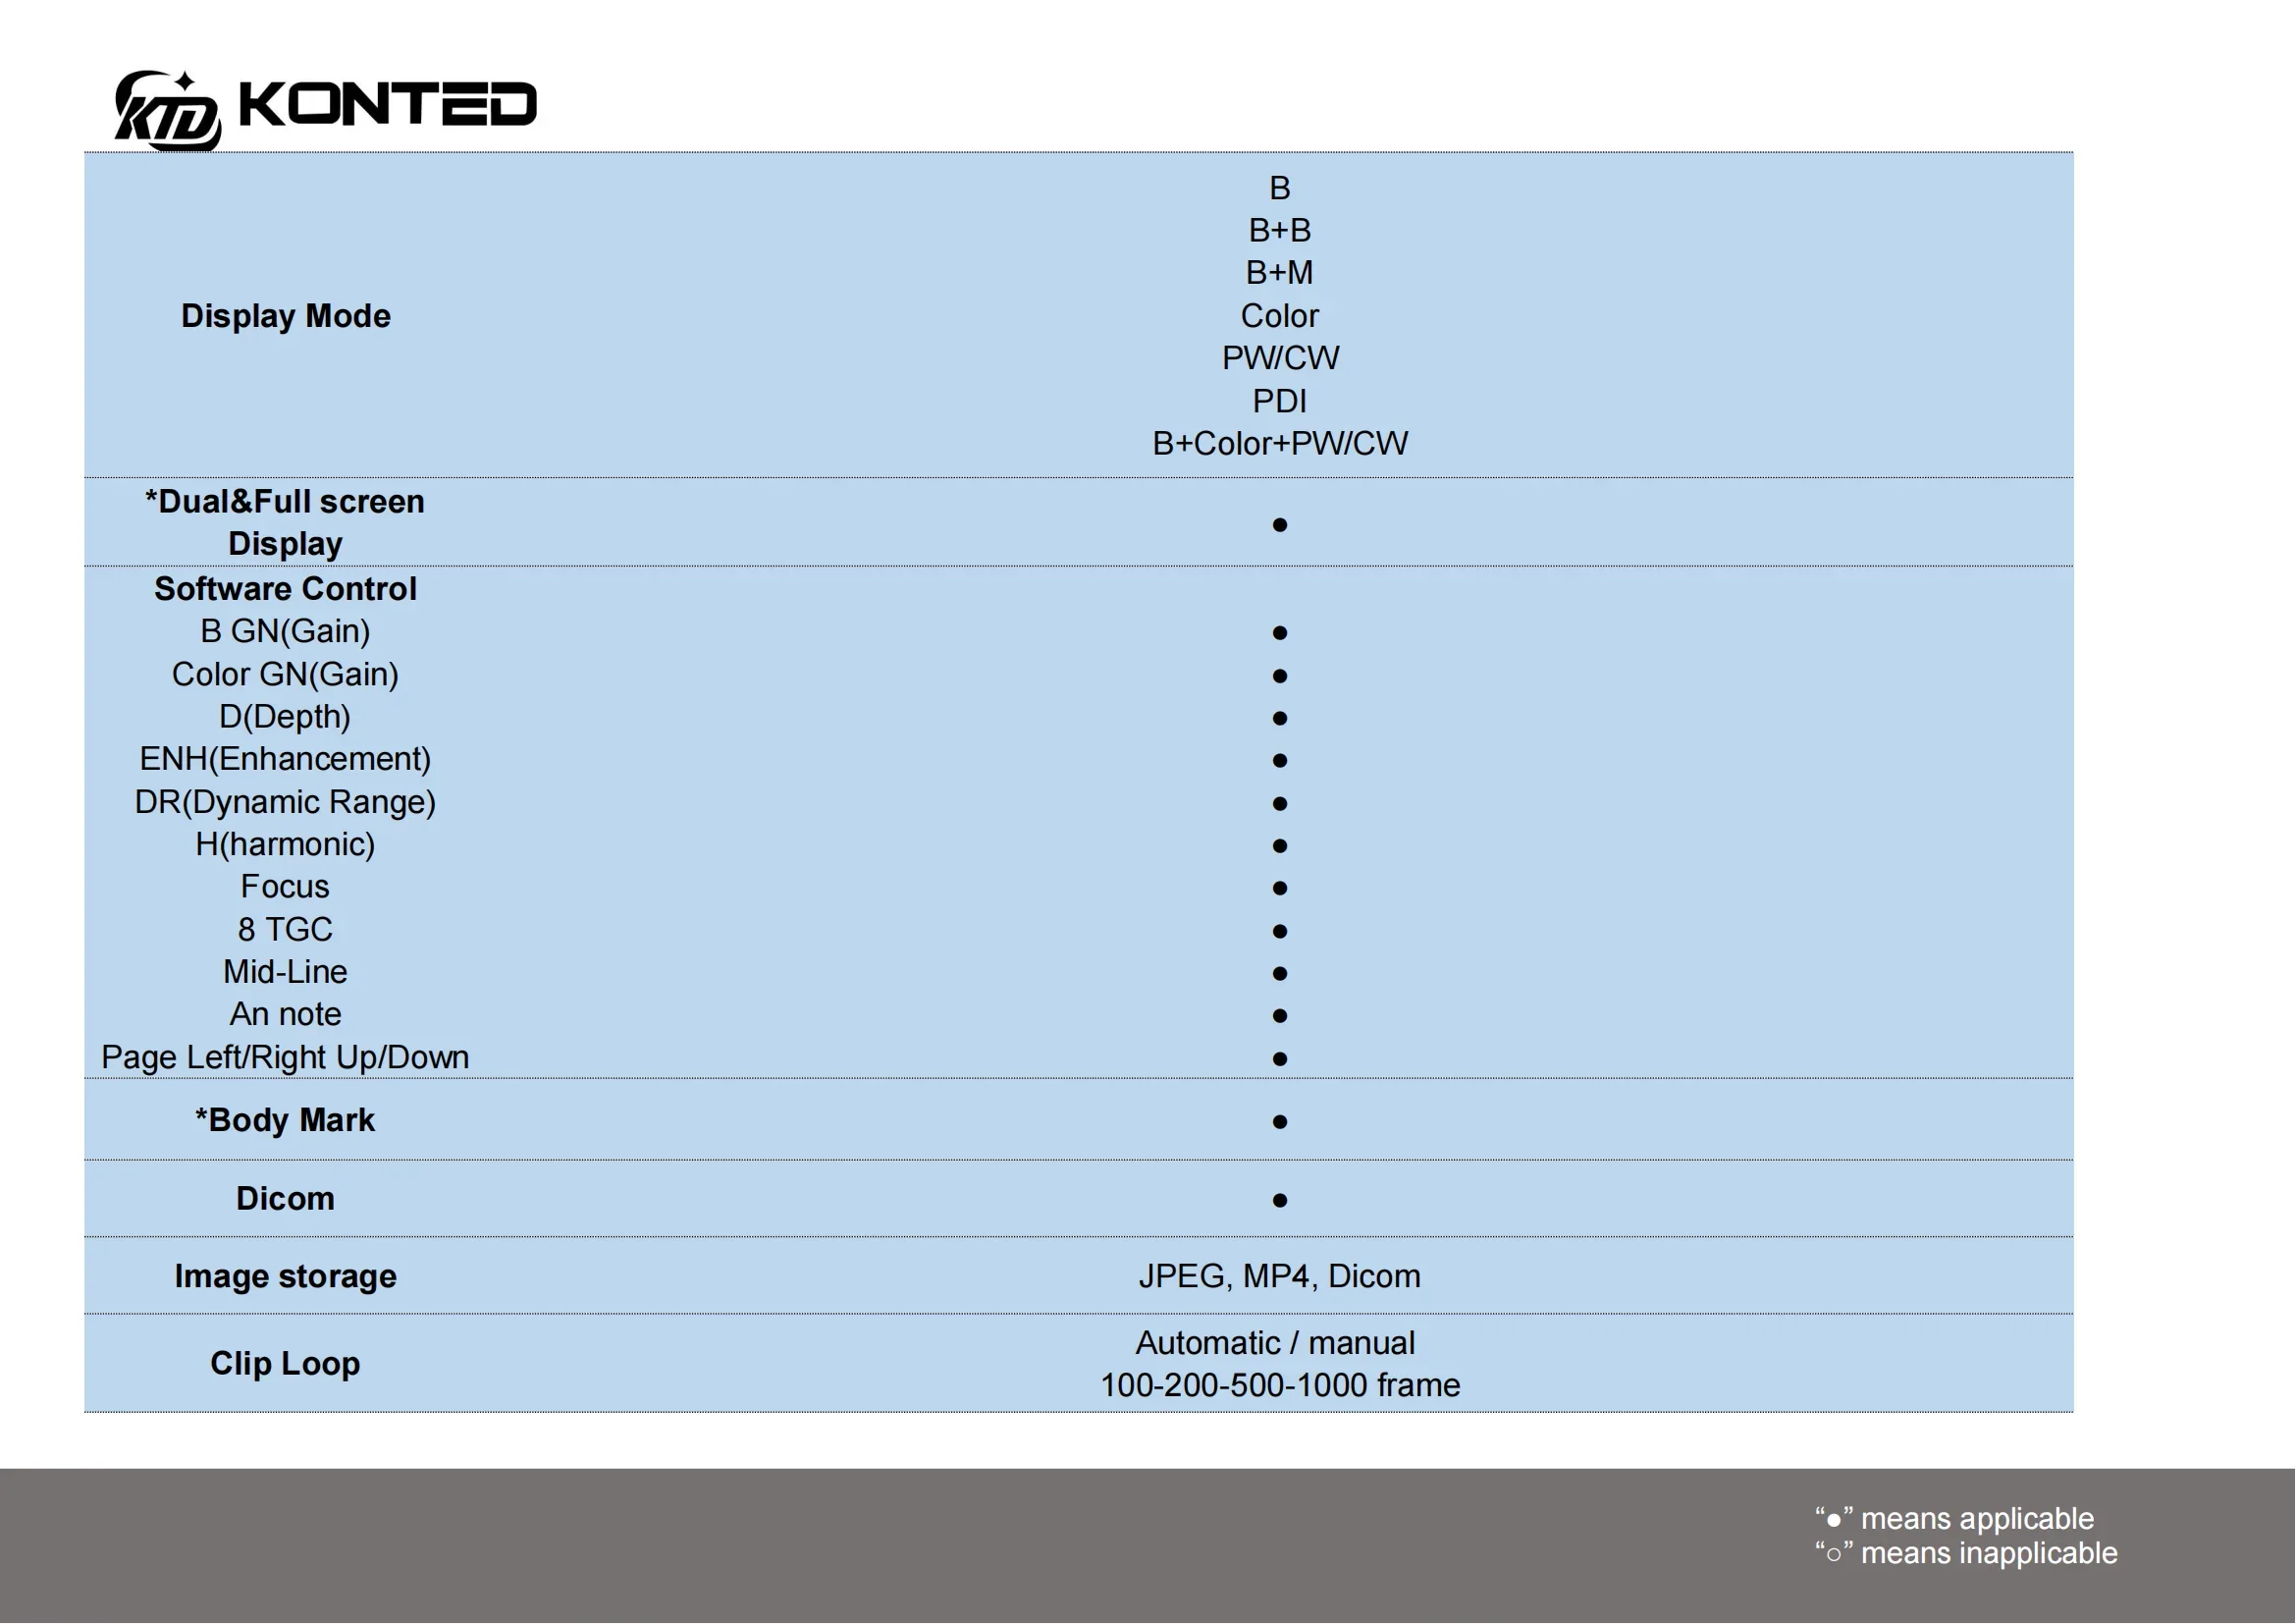

Convex Probe Parameters

-Scanning system: array sweep

-Frequency: 3.5MHz

-Probe element: 80

-Depth: 90-200mm

-Field of view: 80 degree

-Display mode: B,BM

-Image gray scale: 256 level

-Gain:30-105Db

-Measure: distance, area, obstetrics and other

GA(CRL),GA(BPD),GA(GS),GA(FL),GA(HC),GA(AC)

-Language: English, Russian, Italian, Spanish, Chinese, Portuguese

-Power: by built-in battery

-Power consumption: 10W (probe run) /2W (probe stop)

-Battery last: 3 hours

-Footprint: 156mmx60mmx24mm

-Weight: 308 g

Convex Probe Pictures: